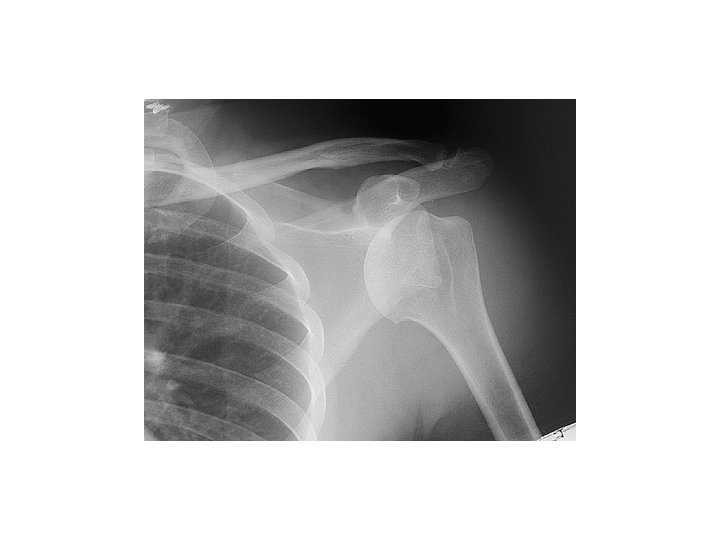

Hill-Sachs

Complications of anterior glenohumeral dislocation and reduction • Neurovascular – neuropraxic and recover in days-weeks • Fractures – Hill-Sachs – 11 -50% of ant dislocations. May be higher if consider minor compression fractures – Bankart – ant glenoid rim #. 5% of cases. – Avulsion # of greater tuberosity in 10 -15%.